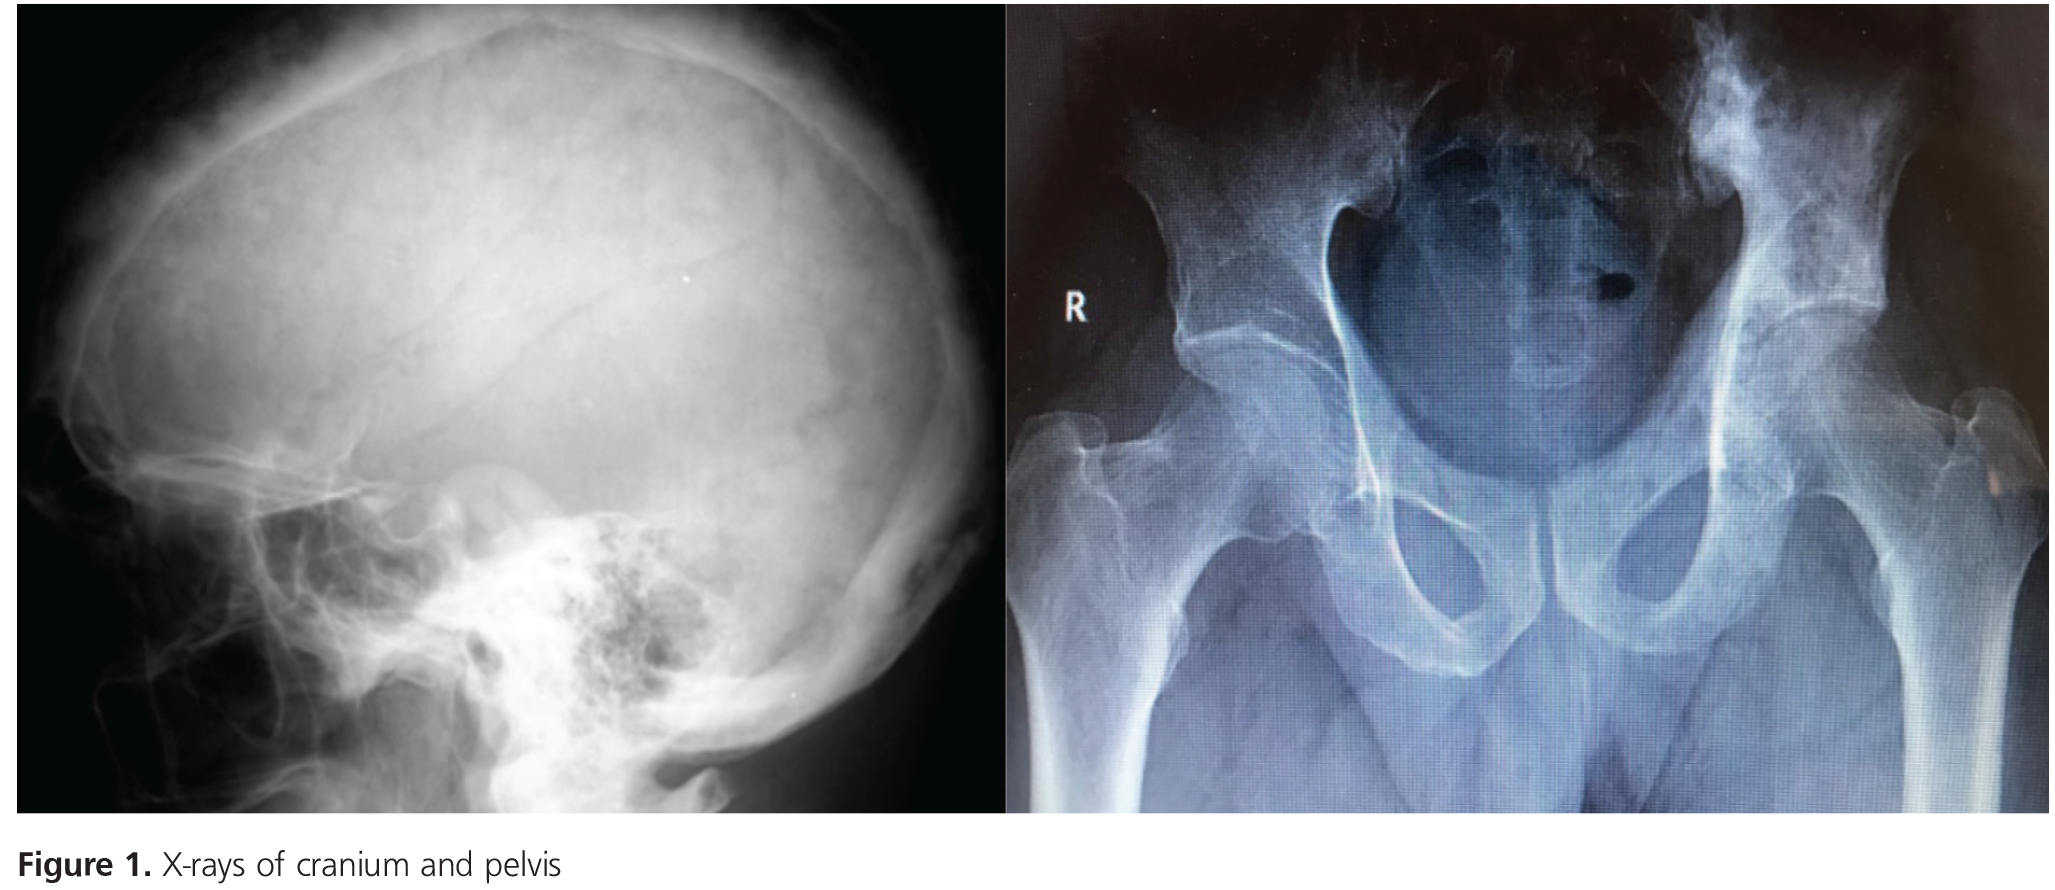

Paget’s Disease Diagnosed on Cranial and Sacroiliac Involvement in Contrast to Normal Alkaline Paget's Disease Sacroiliac Joint this case demonstrates comorbidity with paget disease and possible ankylosing spondylitis. sacroiliac involvement in paget's disease leads to joint fusion by cartilaginous destruction and should. Osteoradionecroses also presents as uniform or multiform osteosclerosis. Of si joints can be seen in paget disease either unilaterally or bilaterally [10]. in this patient, paget’s disease involves both sides of the. Paget's Disease Sacroiliac Joint.

Pagets disease of bone a chronic bone disorder characterised by excessive abnormal bone Paget's Disease Sacroiliac Joint in this patient, paget’s disease involves both sides of the fused sacroiliac joints with confluent pagetic bone across the joints. this case demonstrates comorbidity with paget disease and possible ankylosing spondylitis. Of si joints can be seen in paget disease either unilaterally or bilaterally [10]. specifically, the radiograph of the lumbar and sacral regions showed irregular sclerotic. Paget's Disease Sacroiliac Joint.

Paget's disease Signs & Symptoms Paget's Disease Sacroiliac Joint as (also known as bechterew disease and marie strümpell disease) is a seronegative spondyloarthropathy, which. in this patient, paget’s disease involves both sides of the fused sacroiliac joints with confluent pagetic bone across the joints. Osteoradionecroses also presents as uniform or multiform osteosclerosis. specifically, the radiograph of the lumbar and sacral regions showed irregular sclerotic changes of. Paget's Disease Sacroiliac Joint.